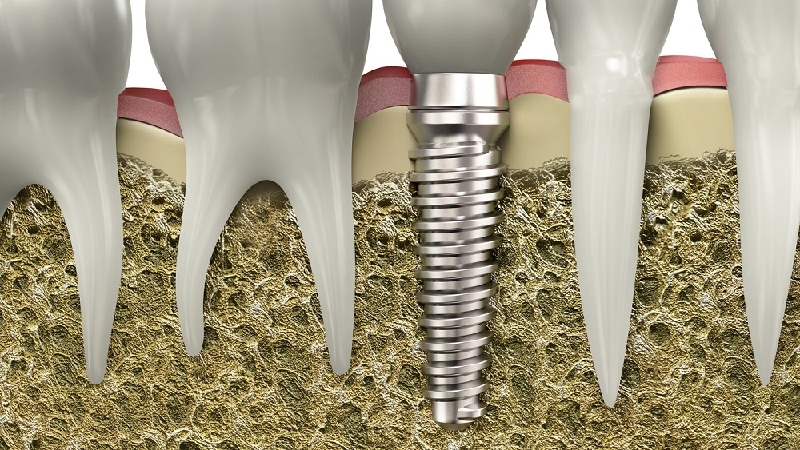

جای گذاری اصولی پایه ایمپلنت درون فک

میزان تراکم مورد نیاز استخوان فک بیمار

میزان سرعت بهبود و جوش خوردن ایمپلنت به استخوان

نیاز یا عدم نیاز بیمار به عمل پیوند استخوان

جایگذاری فیکسچر ایمپلنت دندان درون استخوان فک: ۱۵ تا ۲۰ دقیقه

گذراندن طول مدت خاصی برای جوش خوردن ایمپلنت و استخوان فک: ۳ تا ۶ ماه

انجام ایمپلنت فوری دندان از پرطرفدارترین انواع روش ایمپلنت بوده که در فرآیند کاشت آن پس از درآوردن ریشه، بین ۴ تا ۷ ماه زمان برای ترمیم شدن استخوان فک نیاز است. هنگامی که ریشه دندان را از استخوان فک و لثه خارج میکنند، بلافاصله جای خالی آن حفره، با فیکسچر پر میشود و ایمپلنت به بافت های اطراف پیوند خواهد شد.